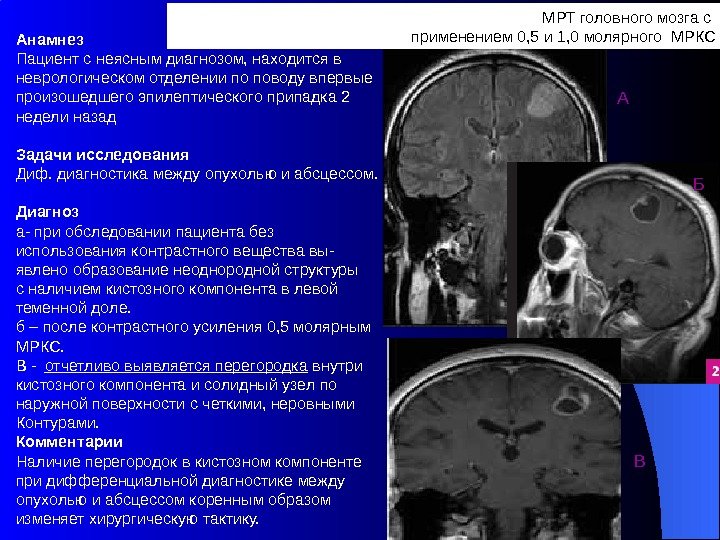

Компьютерная томография в неврологии презентация - 86 фото